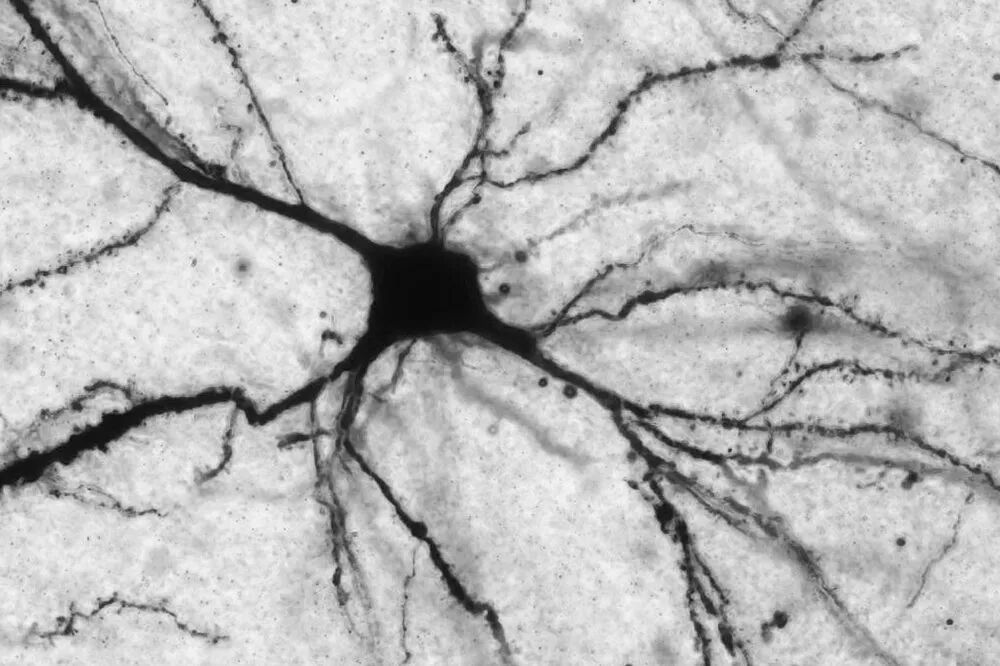

什么是抑郁症?

抑郁症是一种常见的心境障碍,抑郁症不是简简单单的悲伤,它还会影响到我们的思维、感受以及日常活动能力,它会让你的生活陷入僵滞,无法工作,无法学习,无法享受生活,甚至无法正常进食、睡觉。而那种伴随抑郁症而来的无助感、无望感以及无价值感(所谓的「三无」症状)也许会让你的生活变得异常沉重。

有些人形容抑郁症,说它就像是一个吞没人的黑洞,有人说它就像是我们头顶的一片长久不消散的乌云,有人说它是一只黑狗,像影子一样时时刻刻跟随着我们,而著名作家威廉·斯泰隆(William Styron)曾在他晚年的自传里这么形容他与抑郁症相处的生活,他说,抑郁症就像是「新英格兰夏日葱绿中的一片铜锈」。

也许对于有些疾病来说,我们能找到确定无疑的病因,比如说传染病,我们只要知道是什么病原体导致的疾病,就可以对因下药,但是抑郁症要远比这复杂。抑郁症不是由单个病因所导致的,它不仅仅只是我们大脑中某些化学物质的失衡,不仅仅只是我们遗传基因的素质,不仅仅只是生活中的一些负性事件对于我们的影响,也不仅仅只是我们大脑结构的某些改变。它是由生物、心理和社会三个不同层面的因素共同作用所导致的。换句话说,基因发挥了作用,神经递质发挥了作用,大脑结构发挥了作用,同时,你的生活方式、你处理生活事件的能力、你的社交圈、你的经济条件和你所居住的环境等等,也都在抑郁症的发病中扮演了一定角色。